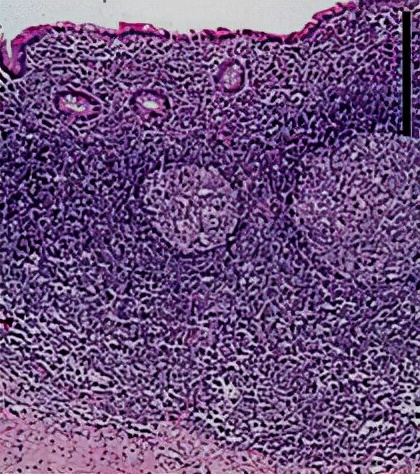

(二)病因和病理类型 1.病因 (1) 阑尾管腔阻塞:淋巴滤泡增生 、粪石、异物、肿瘤等。 (2)细菌入侵:G-杆菌及厌氧菌。 (3) 阑尾先天畸形。

2.病理类型

1.急性单纯性阑尾炎 |

各层水肿和中性粒细胞浸润,黏膜表面小溃疡和出血点 |

阑尾管腔阻塞 |

2.急性化脓性阑尾炎 |

脓性渗出物附着 |

炎症加重 |

3.坏疽性及穿孔性阑尾炎 |

阑尾管壁坏死或部分坏死,呈紫黑色或黑色 |

加剧可发生穿孔 |

*阑尾周围脓肿 |

化脓坏疽时,大网膜移至右下腹,将阑尾包裹并形成粘连 |

形成炎性包块或阑尾周围脓肿 |